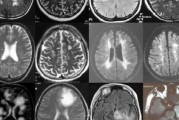

在医学领域,脑瘤的治疗一直是一项复杂且挑战性的任务。对于许多患者来说,放疗是治疗脑瘤的重要手段之一。然而,为什么脑瘤放疗需要一个月的时间?这是否意味着患者的病情无法挽回?本文将围绕这些问题进行解答,并...